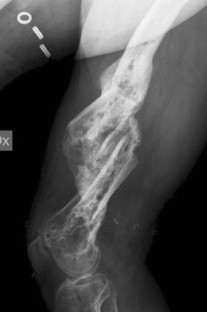

Fig. 1

Fig. 2

Fig. 3

Fig. 4

Fig. 5

Fig. 6